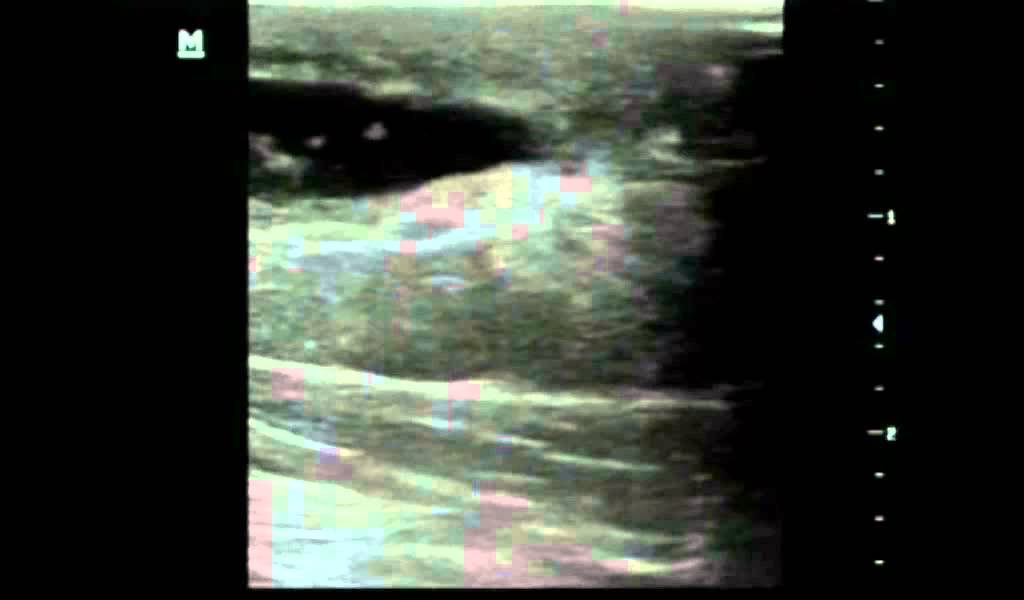

WebComo ya sabes, el seroma es la complicación de una cicatrización en la que hay parte del tejido de la piel que no ha llegado a cerrar bien. Esto ha provocado una bolsa donde se.

WebEl seroma tardío es una complicación que puede darse después de una cirugía plástica. Cuando se reduce la grasa o el volumen de una zona concreta. Por ejemplo, en el caso. WebEl seroma es la acumulación de líquidos corporales transparentes en un lugar del cuerpo de donde se ha extirpado tejido mediante cirugía. WebEl seroma es una posible complicación en intervenciones quirúrgicas como la mamoplastia de aumento. Cuando surgen se forman acumulaciones de líquido. WebHe hecho varias preguntas sobre mi complicación en el pecho izquierdo después de mastopexia. Se creó un seroma enorme que acabó abriendo 3 puntos por la. Web¿Qué es un seroma? El seroma es una acumulación anormal de fluidos serosos. Un líquido seroso es aquel que se parece al suero, de color amarillo pálido y. WebUn seroma es una complicación que puede ocurrir como resultado de la cirugía. Implica la acumulación de líquido en un tejido u órgano. Muy a menudo, se. WebUn seroma es una acumulación de líquido compuesto de grasa, linfa y suero de características inflamatorias (no infeccioso), normalmente claro, de aspecto similar. Web¿Qué es un seroma en el pecho? Un seroma es la acumulación de líquido en un espacio o cavidad que ha sido formada en una intervención quirúrgica. Tras una herida es.

WebUn seroma es una acumulación de líquido compuesto de grasa, linfa y suero de características inflamatorias (no infeccioso), normalmente claro, de aspecto similar. Web¿Qué es un seroma en el pecho? Un seroma es la acumulación de líquido en un espacio o cavidad que ha sido formada en una intervención quirúrgica. Tras una herida es. WebEl Seroma es la acumulación de liquido alrededor del implante mamario que puede producirse después de una cirugía de aumento de pecho. Es un liquido inflamatorio,.